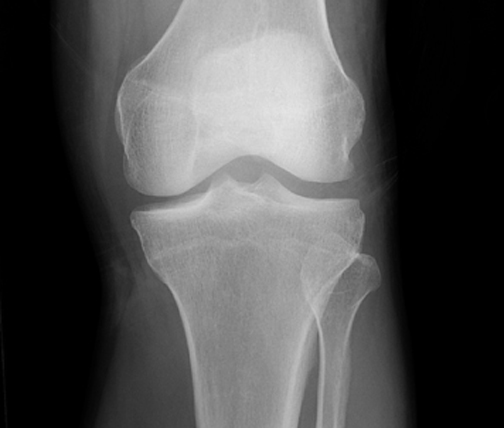

Identify the structures seen. Click the image for labeling.